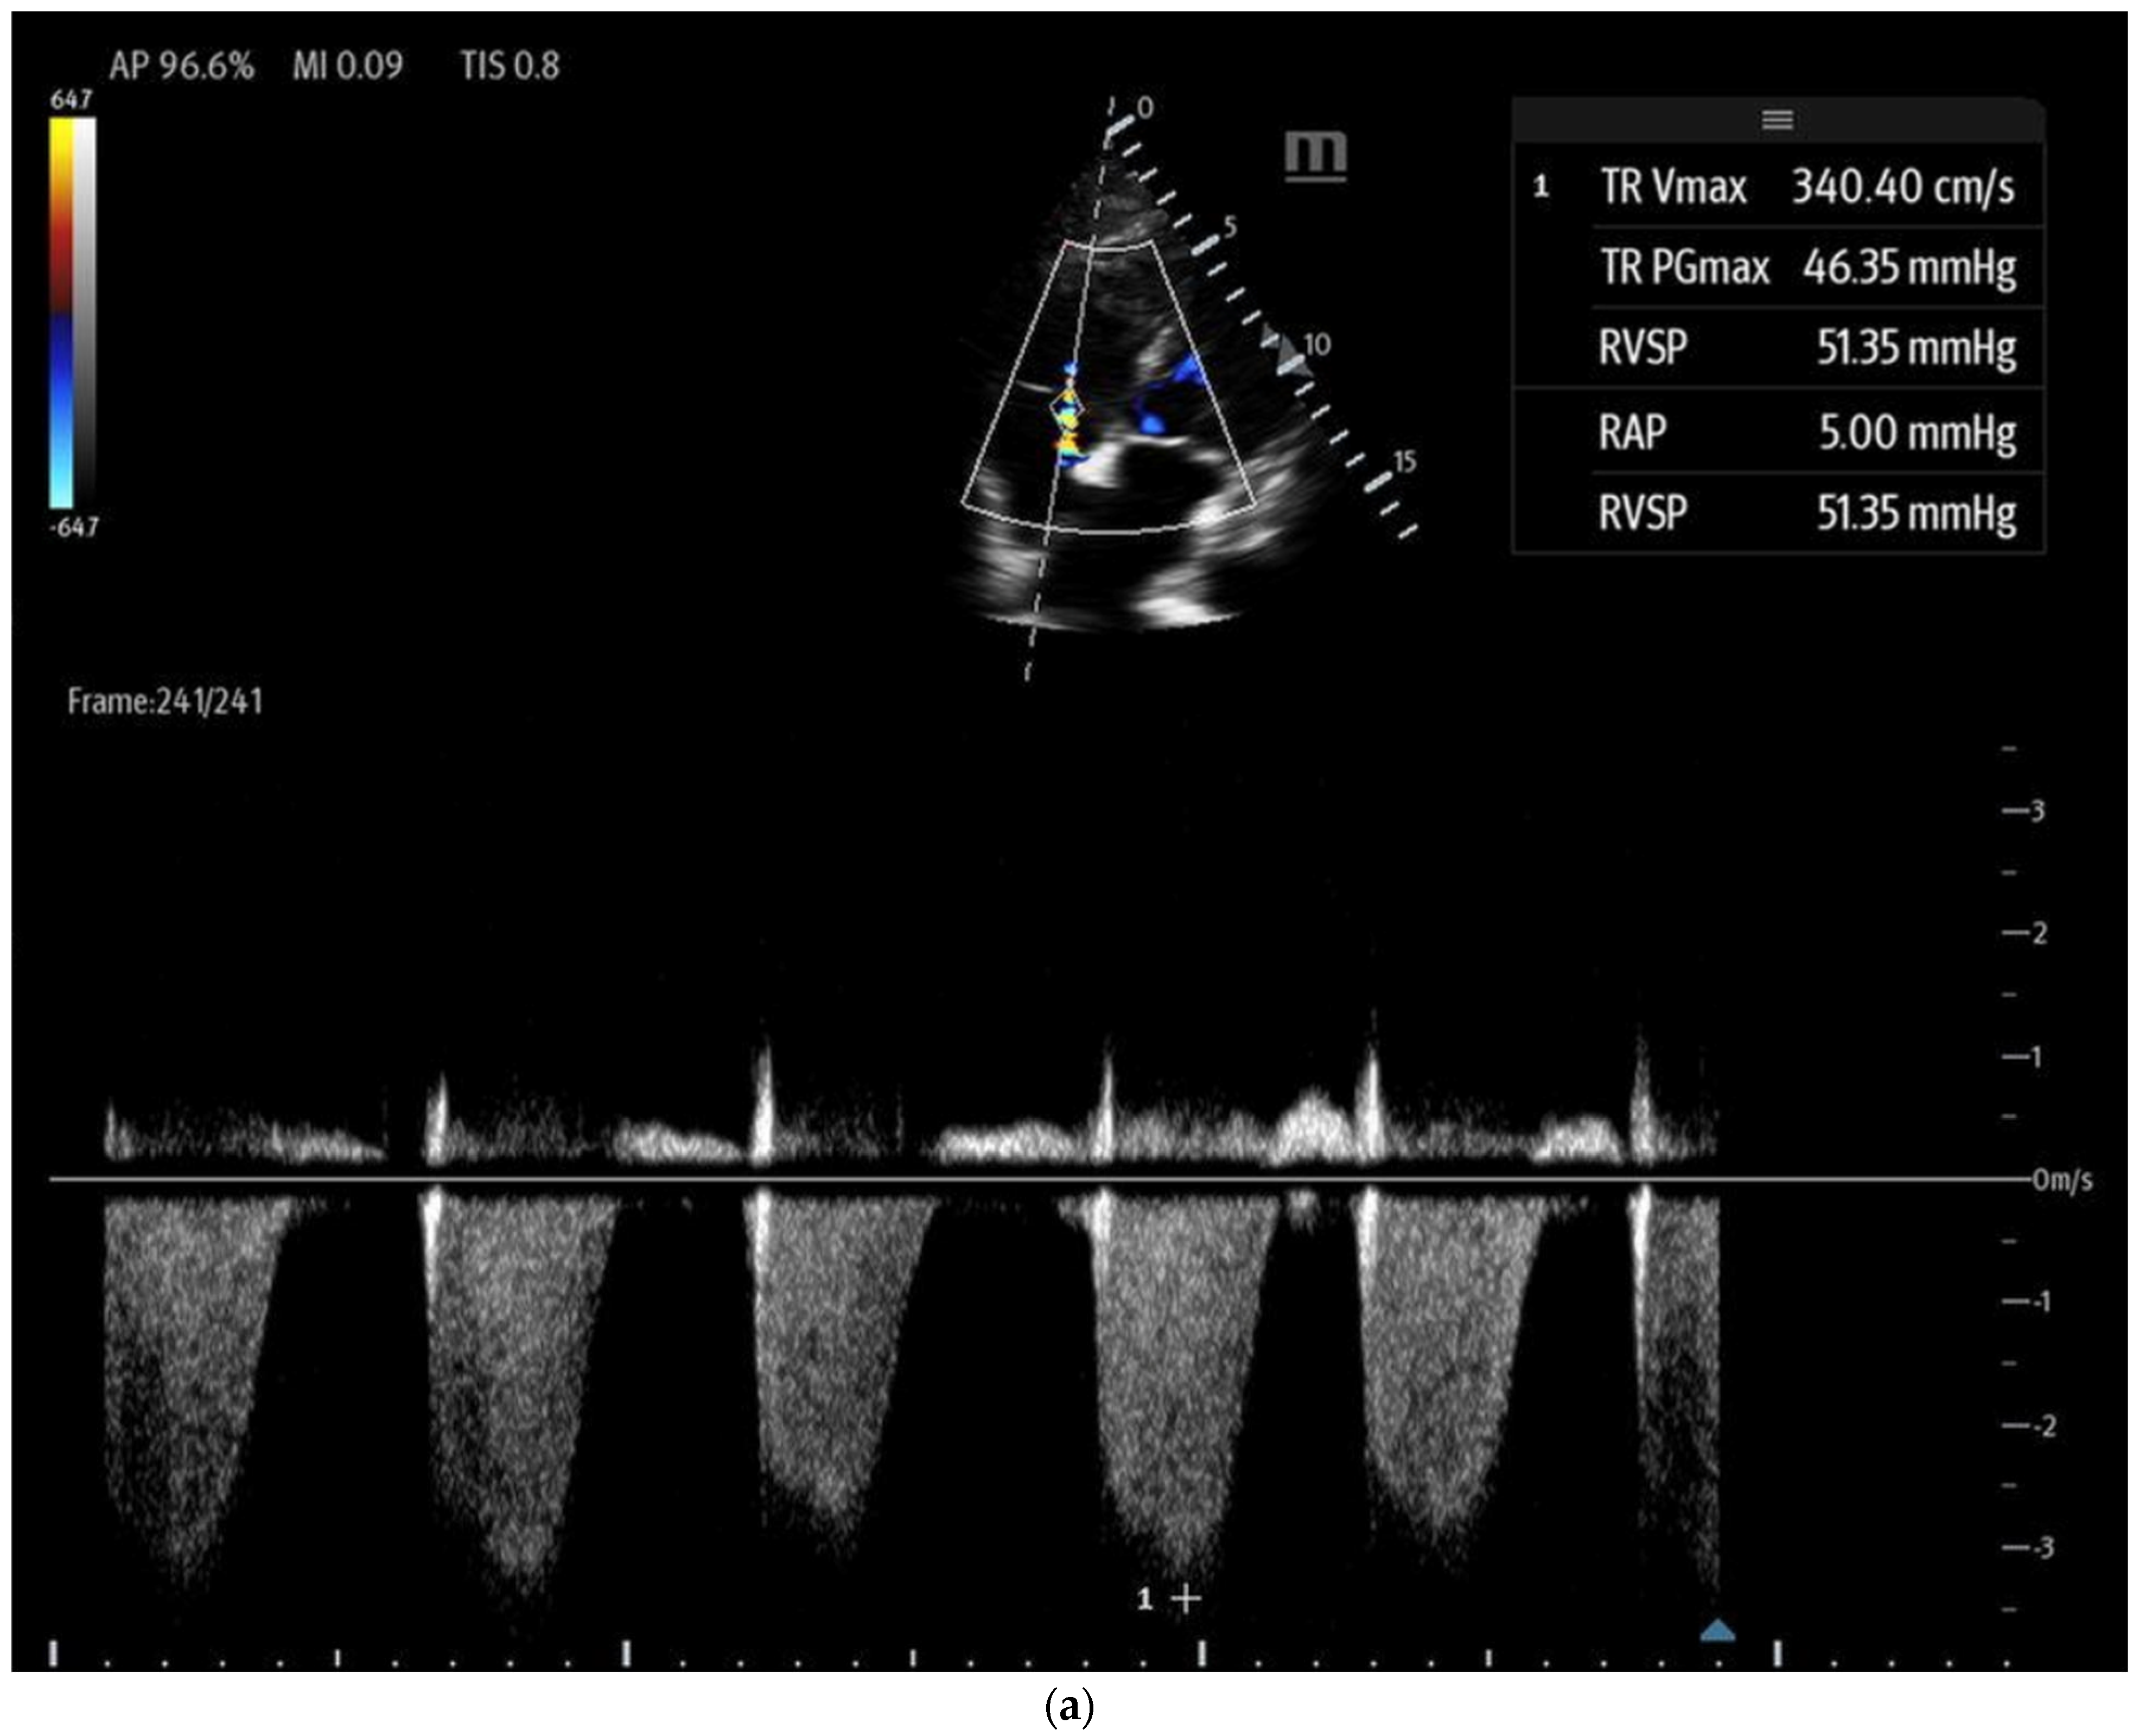

- Tricuspid regurgitation (TR) jet velocity: Pulmonary artery (PA) pressures can be estimated using TR jet peak velocity (Figure 8a). The evidence suggests that in the right clinical context, a TR jet velocity greater than 2.8 m/s is an independent predictor of pulmonary hypertension, while a velocity > 3.4 m/s strongly indicates this condition [35,43,44]. However, this method has limitations as TR jet velocity may underestimate PA pressures in cases of severe TR and is unreliable when TR is insufficient for evaluation [43]. Additionally, this technique cannot differentiate pulmonary hypertension from other causes of RV outflow obstruction, such as pulmonary or RVOT stenosis [44].